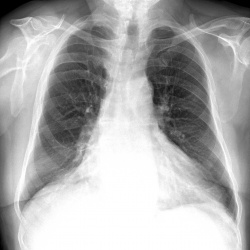

Пациент 60 лет. дообследуется после ФГ. Из жалоб одышка. С избыточной массой тела. Архива нет. Смутил правый корень. высокое стояние правого купола диафрагмы.